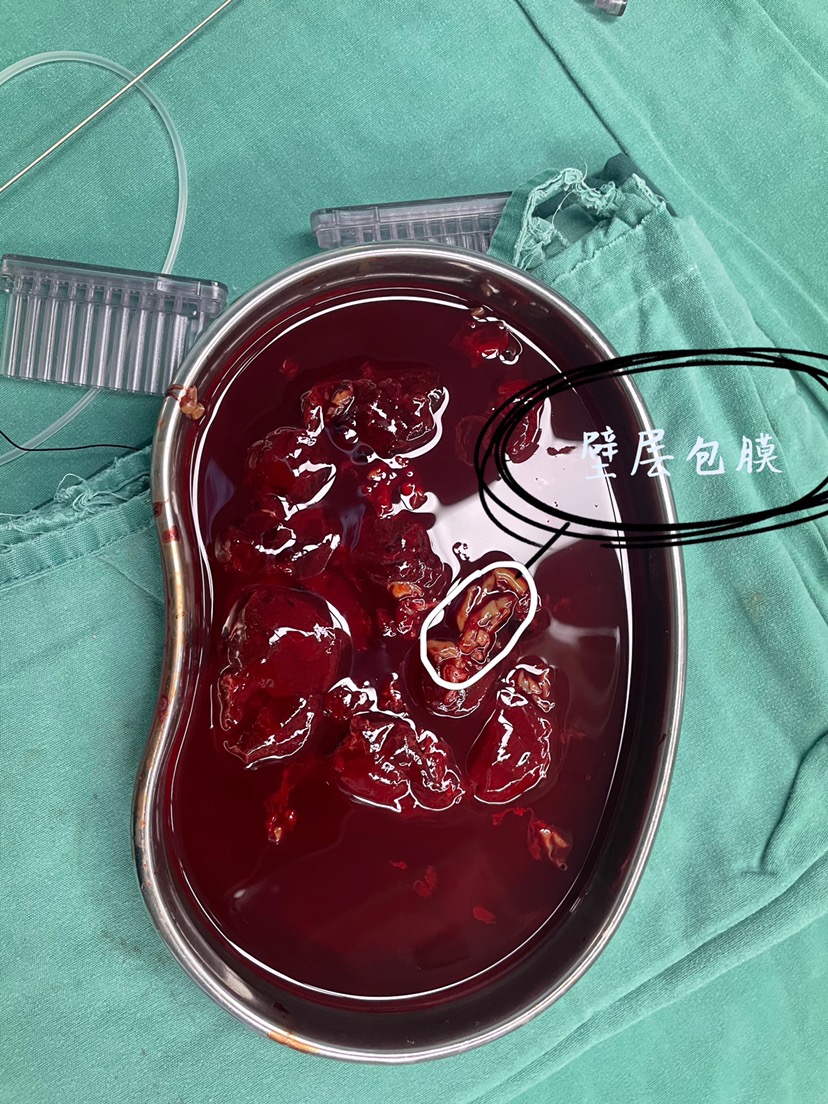

术中所见如下:

硬膜下血肿,打开硬脑膜,见明显的包膜。

清除大量“果冻”样血凝块,同时剔除包膜

2、该患者大部分血肿呈“果冻”样血凝块,单纯钻孔可能效果不佳,开颅应该是正确的选择。

3、剔除包膜预防复发,脑组织复张会更好。